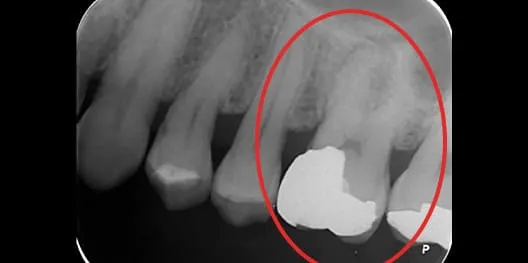

治療前 治療前

治療後 治療後

感染根管治療の症例

主訴

左上の歯ぐきが腫れている

治療内容

感染根管治療

患者さまの年齢

64歳

治療期間

2週間(治療回数は2回)

治療費用

¥132,000+再診料¥3,300(税込)